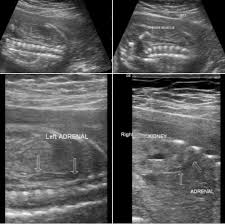

Ultrasound Images Of The Kidneys Reveal Multiple Indentations Short Arrows Of The Renal Cortex Diagnostic Medical Sonography Ultrasound Sonography Ultrasound

Ultrasound Images Of The Kidneys Reveal Multiple Indentations Short Arrows Of The Renal Cortex Diagnostic Medical Sonography Ultrasound Sonography Ultrasound from www.pinterest.com